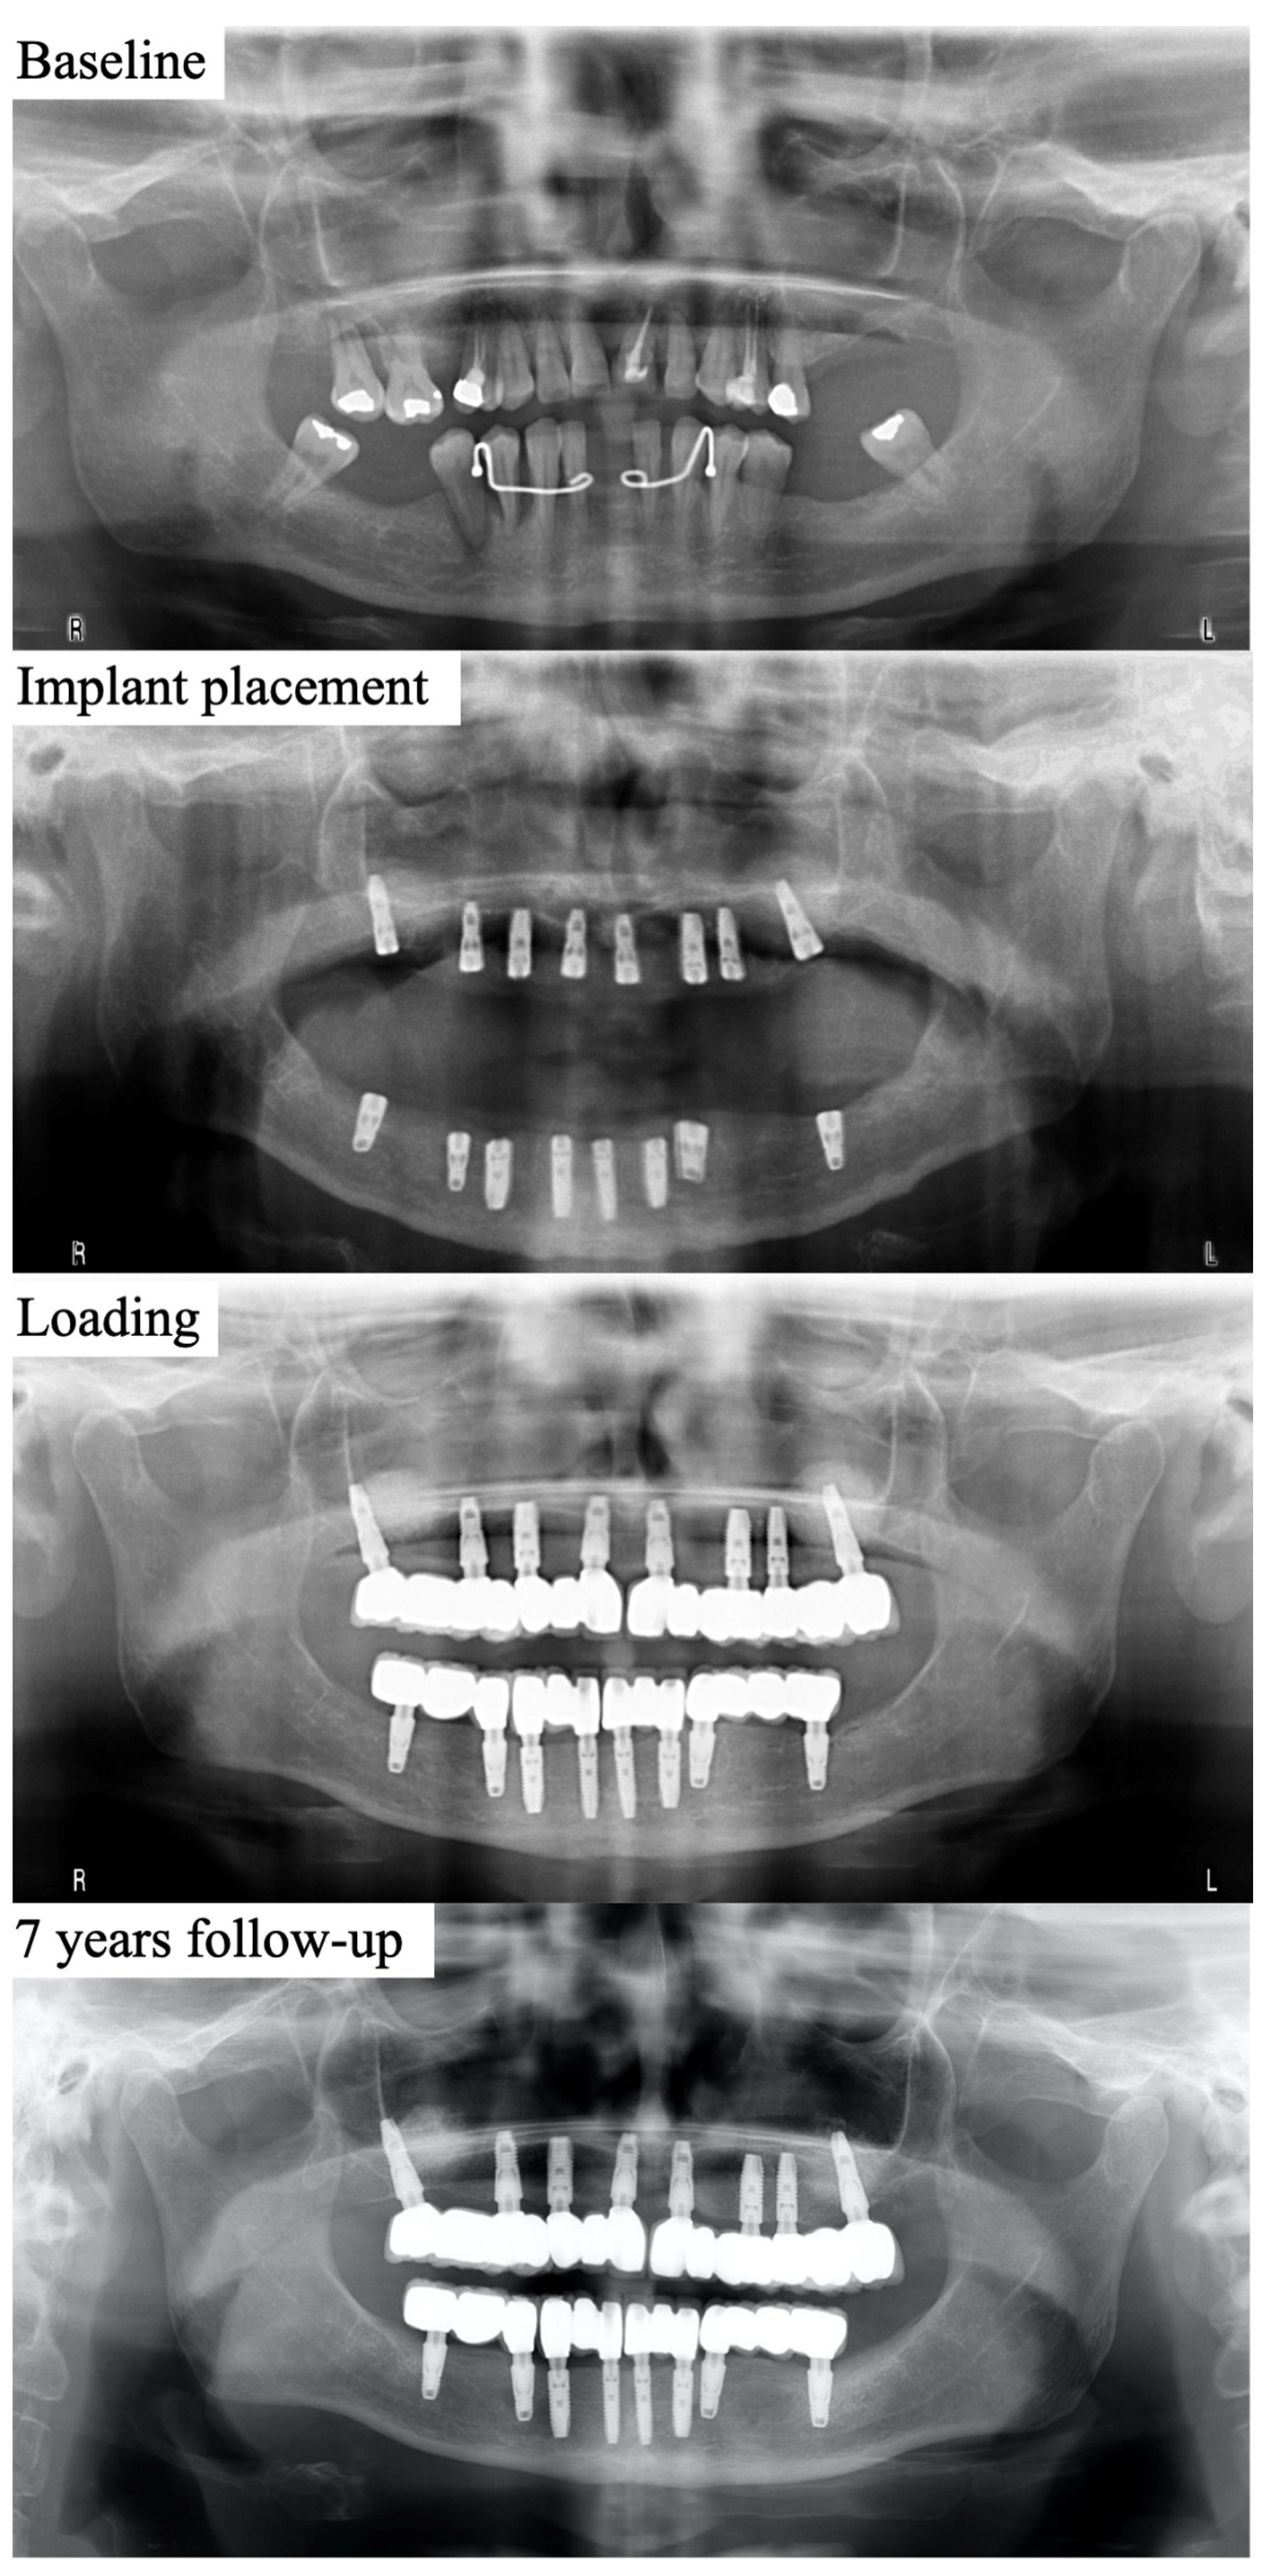

2.2. Surgical and Restorative Procedures

2.3. Radiographic Evaluation of MBL